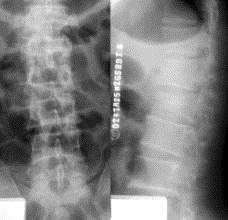

问题 病历摘要: 患者×××,男性,21岁,不慎从3米高处坠落,双足着地,出现双足跟肿胀疼痛,腰痛不能站立。查体:腰1棘突有压痛和叩击痛,双足足跟部肿胀,触痛(+),双下肢感觉正常,双足伸足母、伸趾正常,双膝关节伸屈正常。 该患者的诊断是: 提示:该患者腰椎 X线如图

选项 A、腰1椎体陈旧性骨折 B、腰1椎体骨折并后凸畸形 C、腰1椎体骨折并椎管狭窄 D、腰1椎体爆裂骨折 E、腰1椎体骨折脱位 F、腰1椎体压缩性骨折

答案 F